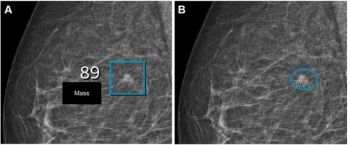

Emerging research suggests that combining full-field digital mammography and whole-breast ultrasound tomography provides superior sensitivity in detecting BI-RADS 4 lesions and superior specificity in diagnosing BI-RADS 3 lesions than mammography alone in women with dense breasts.

In a retrospective study involving nearly 119,000 women, researchers found that implementation of AI into mammography screening increased the positive predictive value by 11 percent, increased small cancer detection by 8.3 percent and reduced reading workload by approximately 33 percent.